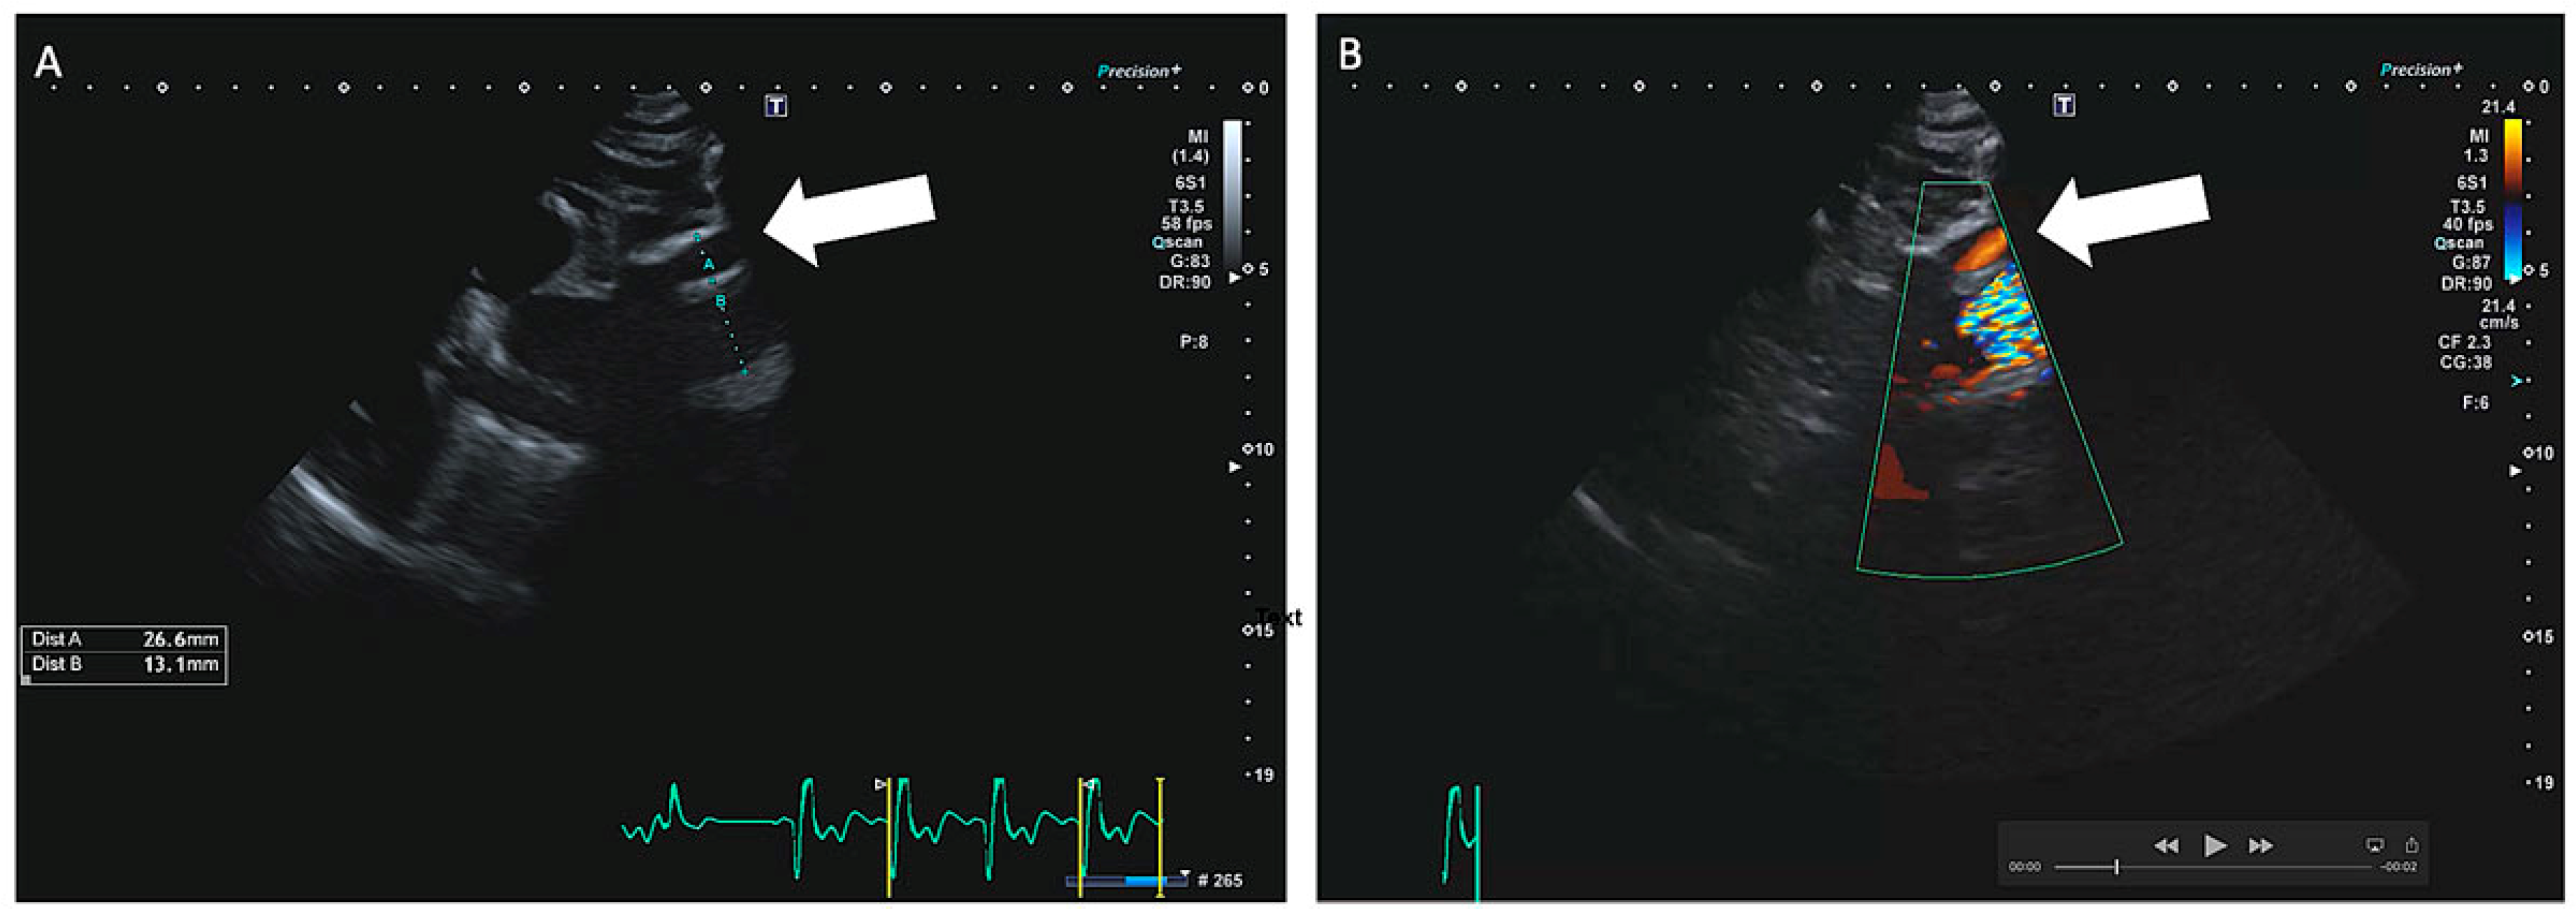

Bei einem 63-jährigen Patienten besteht ein Status nach mechanischem Aortenklappenersatz 1994 mittels St. Jude Medical© 25 mm bei kombiniertem Aortenklappenvitium, notfallmässigem Ersatz der Aorta ascendens mit 30-mm-Gefässprothese und Erhalt der Aortenklappenprothese im hypothermen Kreislaufstillstand bei Aortendissektion Typ A im Jahr 2001 und erneuter Reoperation bei Nahtaneurysmen mit Ersatz der Aorta ascendens und des Aortenbogens mit Haemoshield-Gefässprothese im Jahr 2003. Bei einer routinemässig durchgeführten Nachkontrolle durch den niedergelassenen Kardiologen wurde mittels transthorakaler Echokardiographie (TTE) ein perfundiertes Pseudoaneurysma im Bereich des proximalen Aortengrafts festgestellt (Abbildung 1). Daraufhin wurde der klinisch beschwerdefreie und hämodynamisch stabile Patient zur dringlichen Computertomographie (CT) in ein peripheres Spital überwiesen. Dort bestätigte sich der Verdacht eines Pseudoaneurysma im Sinne eines Nahthaneurysma (ca. 47 × 19 × 44 mm) ausgehend von der Aorta-ascendens-Prothese mit hochgradigem Verdacht auf Graftdehiszenz zwischen Ascendes- und Aortenbogengraft (Abbildung 2).

Abbildung 2. Die präoperative CT-Angiographie (A: frontaler Schnitt; B: transversaler Schnitt) zeigt das perfundierte Nahtaneurysma (weisser Pfeil).